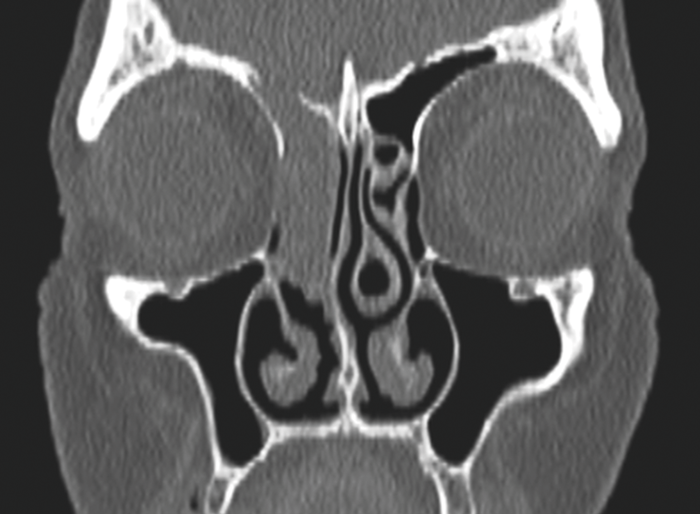

Preoperative sinonasal CT imaging is essential to FESS surgery. Ideally the CT data should be provided in thin-slices (less than 1mm thick) including the full volume of the paranasal sinuses. The images should be available during surgery in a 3 axis viewer, preferably one with the facility for multiplanar reconstruction (MPR).

Before the case, it is helpful to perform an MPR to align the axial slices with the palate and skull-base, while correcting any angulation of the coronal images to obtain symmetric views. Window-levels are optimised for bone definition, rotation corrected for each view, and the views maximised by zoom. We then study the scans from three different perspectives as follows.

Operative CT - sinonasal anatomy

Studying and understanding an individual patient’s radiological anatomy will facilitate a safe and effective dissection. It is usually easiest to identify deviations from ‘normal anatomy’, recognising features such as a concha bullosa, Onodi, and Haller cells to allow operative orientation and maintain safety. The complex anatomy of the frontal recess is defined by the relationships of the basal lamellae of the uncinate process and ethmoidal bulla and their insertions into the lamina papyracea and skullbase. Understanding this anatomy, then demonstrating the same during surgery by probing will then facilitate a complete, safe, and mucosa preserving technique.